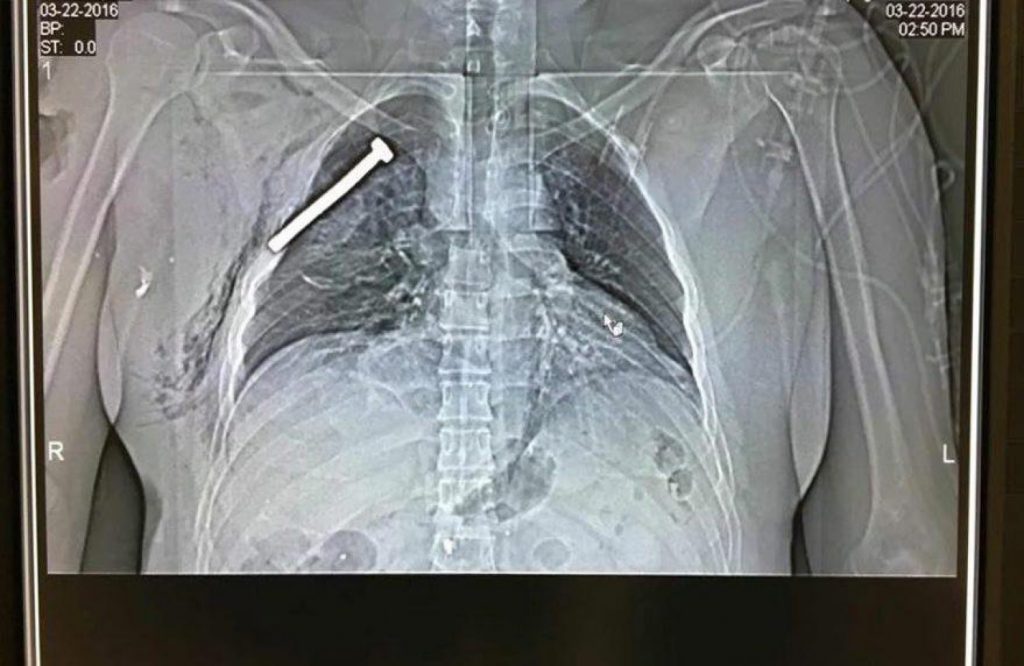

Bruxelles, le armi dei terroristi

Avete una pentola a pressione? Con pochi materiali, alcuni disponibili in ogni casa, potreste creare quella comunemente nota come “pressure cooker bomb”. È ritenuto l’IED improvvisato più facile da realizzare perché, oltre all’esplosivo in sé, può essere realizzato con materiali...